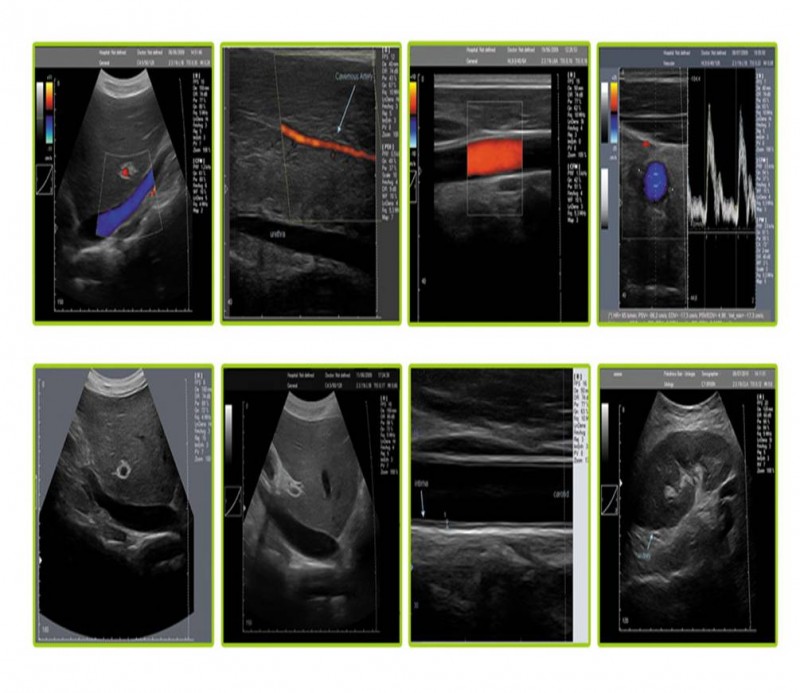

?超聲介入引導(dǎo)系統(tǒng)是針對經(jīng)外周靜脈穿刺中心靜脈置管(PICC)、靜脈中心置(CVC)和各種類型的神經(jīng)阻滯等手術(shù)可視化需求而專門設(shè)計的一款??朴貌食E溆歇毺氐拇┐桃龑?dǎo)系統(tǒng),在幫助醫(yī)護人員獲得高質(zhì)量超聲圖像的同時通過智能化操作引導(dǎo)功能,進行快捷、方便的診斷操作。

超聲介入引導(dǎo)下的深靜脈穿刺和各種類型的神經(jīng)阻滯利用超聲原理實現(xiàn)可視化技術(shù),已經(jīng)逐步成為麻醉學(xué)科發(fā)展的重要方向,另外在淺靜脈置管、PICC置管、CVC置管、胸腔穿刺、術(shù)中影像檢測、在腫瘤科、神經(jīng)外科、腎內(nèi)科ICU、急診急救等方面也廣泛應(yīng)用。